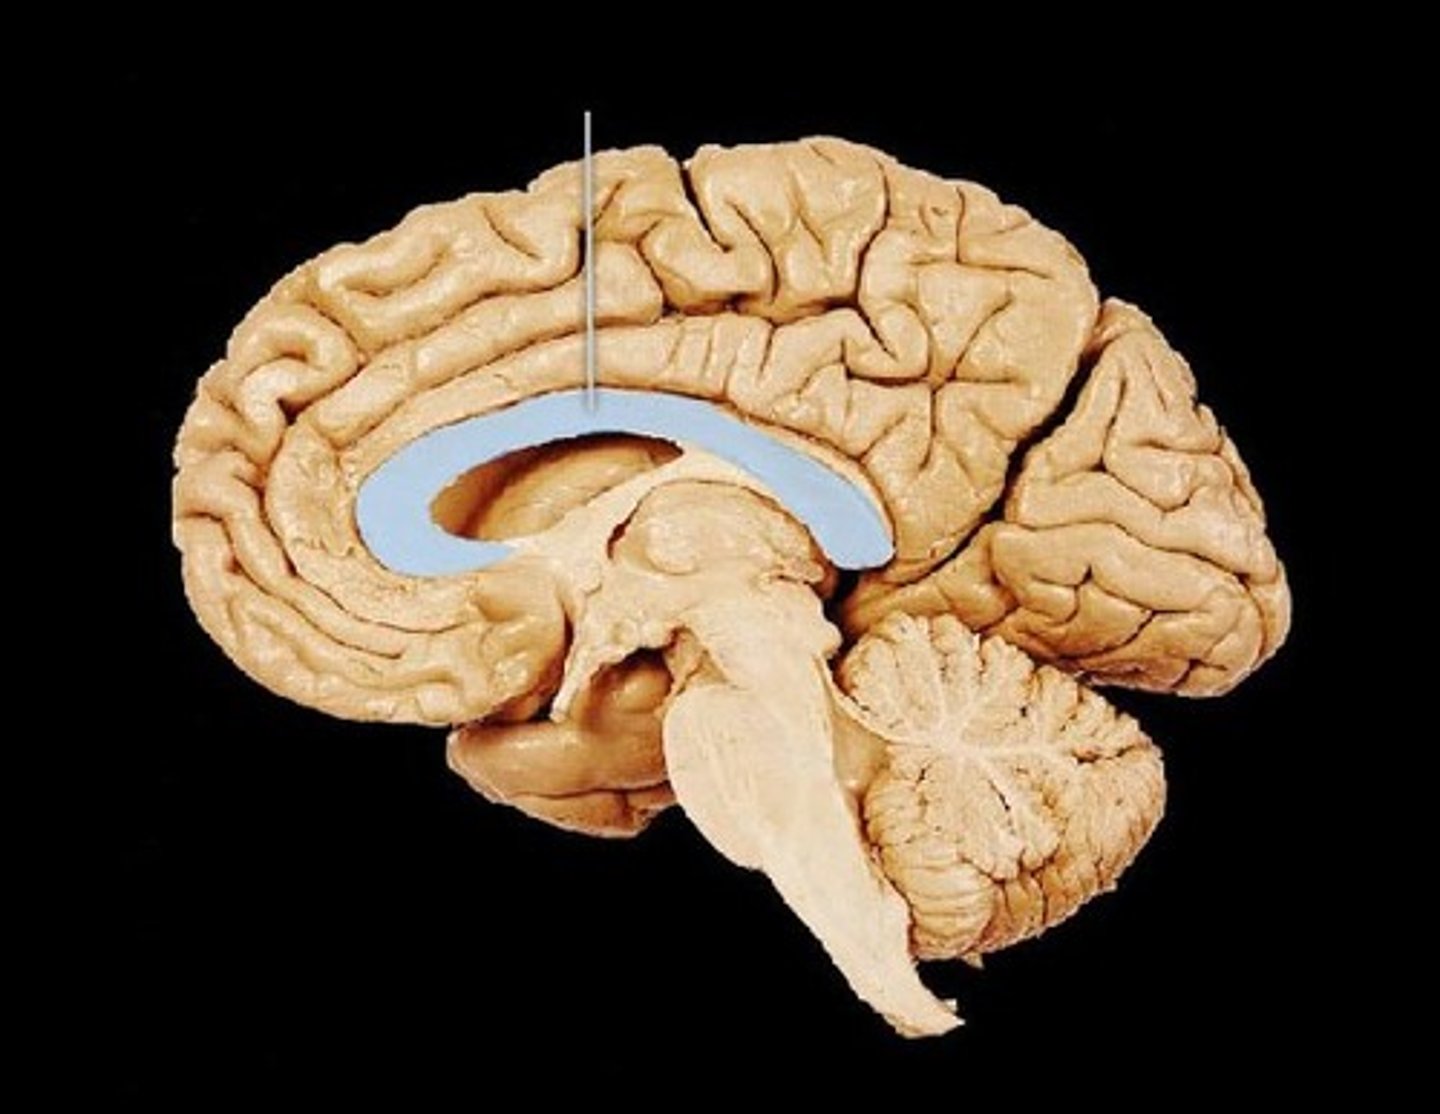

MIdsagittal View of brain

Lateral Ventricle

Corpus Callosum

Fornix